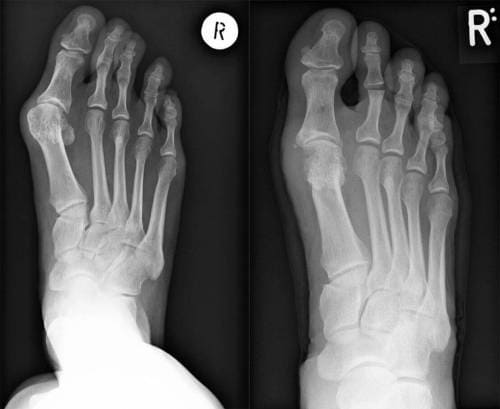

Raggi X delle gambe prima e dopo il trattamento

Operazione per rimuovere l'osso dalla gamba. Dopo aver eseguito una radiografia, il chirurgo ha concluso tragicamente che era urgente un intervento chirurgico per rimuovere il dito storto. L'alluce storto aveva già causato complicazioni alle articolazioni del piede, a causa delle quali alcuni legamenti all'interno del piede erano danneggiati, presto sarebbe iniziata la necrosi e quindi il piede avrebbe dovuto essere amputato.